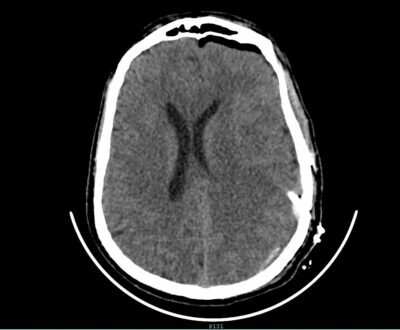

وأوضح رئيس القسم الدكتور زهير هوساوي الذي أجري العملية أن المريض قد قدم لقسم الطوارى وهو يعاني من صداع شديد وفقدان النطق وضعف الحركة بالجانب الايمن من عدة شهور وبعد الفحص السريري والأشعة اتضح وجود اكياس نزفيه بجانب منطقة الحركة والكلام في الدماغ مما استلزم إجراء العملية باستخدام المايكروسكوب والمنظار التي تُعد من أحدث التقنيات العلاجية في هذا المجال وتم ازالة التكيسات في المناطق الدماغية كاملة مع المحافظه على منطقة الحركة والكلام بفضل الله ثم التطور الهائل في مجال الخدمات الطبية والعلاجية الذي تواكبه قطاعاتنا الصحية بدعم واهتمام كبير من القيادة الرشيدة -رعاها الله – وحرصها على توفير أفضل و أحدث الإمكانيات المتطورة تم اجراء العملية بنجاح تام وعودة النطق والحركة لطبيعته السابقة لدى المريض .

مبيناً أن العمليه استغرقت ثلاثة ساعات بمشاركة كلاً من استشاري جراحة المخ والاعصاب الدكتور محمد المشد واستشاري التخدير الدكتور علي الغامدي و الدكتور محسن .